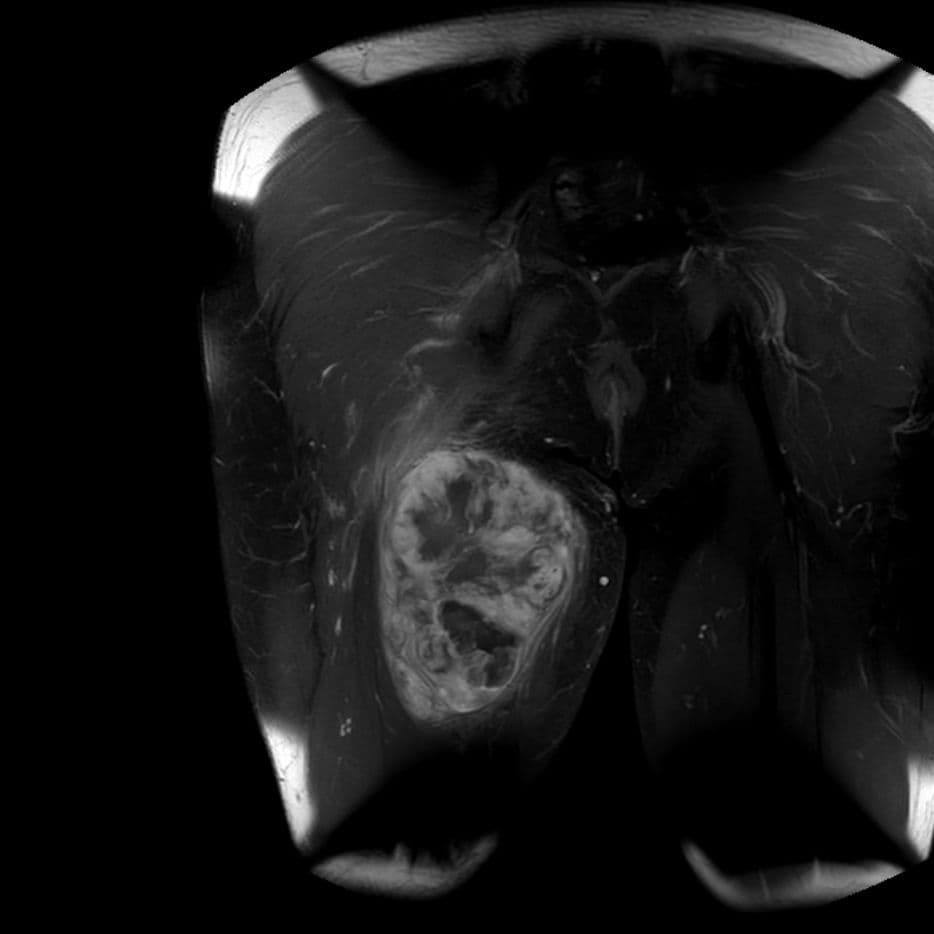

Sarcome de la cuisse à composante mixoïde

MRI